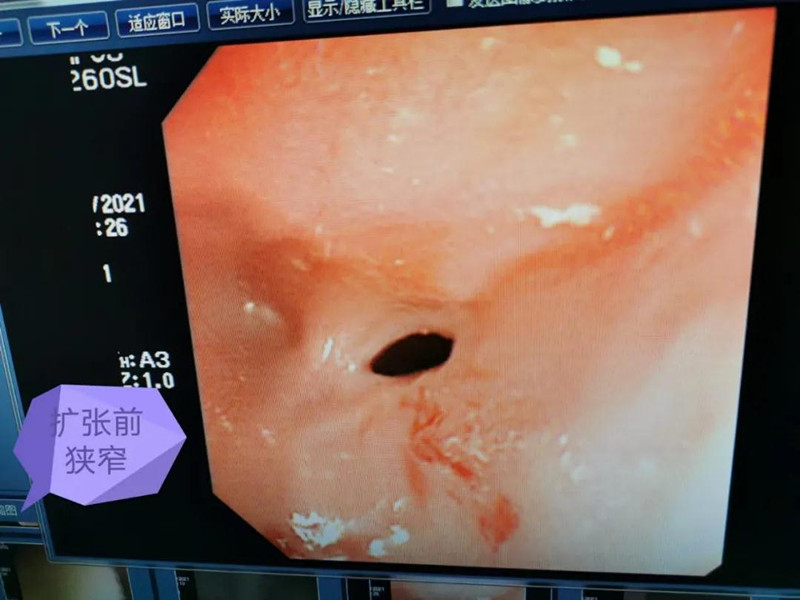

天天6个月了。最近总出现呛奶的情况,后来还出现肺炎症状。在德州扑克游戏网 经食道造影后,医生发现天天的症状是由术后并发症“食道吻合口狭窄”引起的,最窄处仅5mm多一点。食道狭窄球囊扩张术是目前最适合天天的手术了。内镜中心副主任边鹏说,这是一种微创介入治疗,具有创伤小、恢复快、合并症少的优势。2月26日,在麻醉科、内镜中心团队的合作下,边鹏为天天行经内镜下食道狭窄球囊扩张术。术中,边鹏用直径8mm的球囊进行扩张,将原来狭窄的食道扩成直径8mm的宽度。

天天太小,在球囊扩张的过程中,需要格外注意,不能扩张太快,否则会出现穿孔或大出血。所以边鹏每扩张3分钟,暂停3分钟,共扩张了3次。整个扩张过程很顺利,效果也非常好。次日,天天就出院了。在球囊扩张前,小儿内镜下显示,天天食道吻合口狭窄处上端竟有一团纸,家长也不清楚孩子是什么时候吃了纸。因为吻合口处太窄,纸下不去,形成了阻隔,导致天天最近总呛奶,奶汁进入气道,最终出现肺炎。